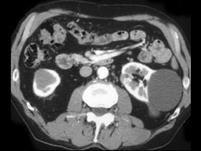

问题 女,45岁,左侧腰背部隐痛不适,请根据所示图像,选择最可能诊断 ( )

选项 A、左肾小肾癌 B、左侧小肾癌合并单纯性肾囊肿 C、左侧单纯性肾囊肿 D、左侧多发性肾囊肿 E、左肾未见异常

答案 B